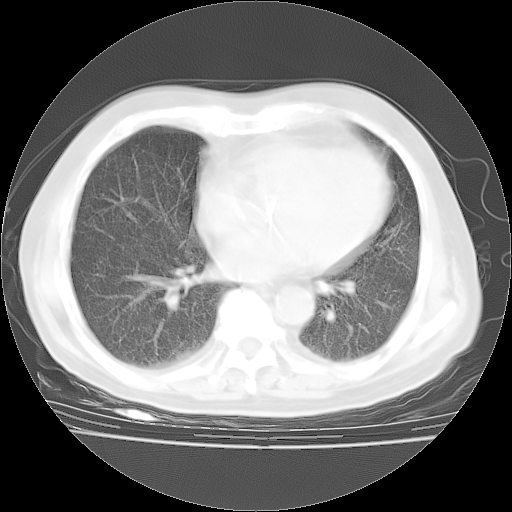

4月28日肺部CT——再次出现类似去年5月9日——透光度降低,“间质性”改变。

4月28日肺部CT——再次出现类似去年5月9日——磨玻璃样、间有“粟粒样”改变。

个人阅读4.14日肺部CT平扫:纵隔窗无异常,但肺窗示:双下肺内、后基底段有片絮状侵润影,部位以后基底段为著,以间质改变为主,呈急性肺泡炎征像,和首次住院影像学有相似之处。仅是个人读片,明日请相关专家再读片哈。其它建议同上。